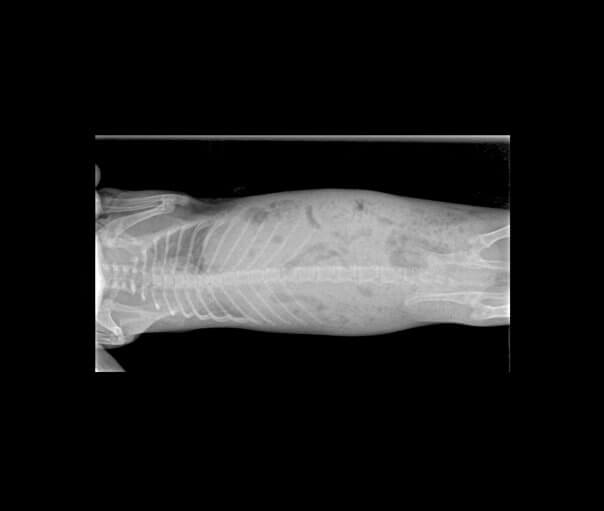

En el cas de l’Audrey, es va recomanar realitzar un cultiu fúngic i una radiografia, ja que les nostres sospites principals eren que patia algun procés respiratori i una infecció de la pell causada per fongs (dermatofitosi).

Una vegada realitzades les proves, es varen confirmar les nostres sospites. Audrey patia una dermatofitosi juntament amb una pneumònia localizada al pulmó dret.